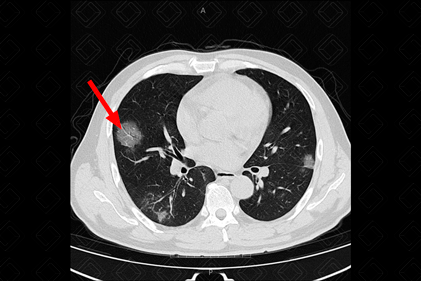

Descrição das figuras 4, 5, 6 e 7: Radiografia e nova tomografia de tórax, realizadas 4 dias após admissão, evidenciando piora dos achados pulmonares. Importante aumento das opacidades em vidro fosco periféricas.

• Diante da evolução desfavorável, pode ocorrer aumento das opacidades em vidro fosco, com surgimento de áreas de consolidação;